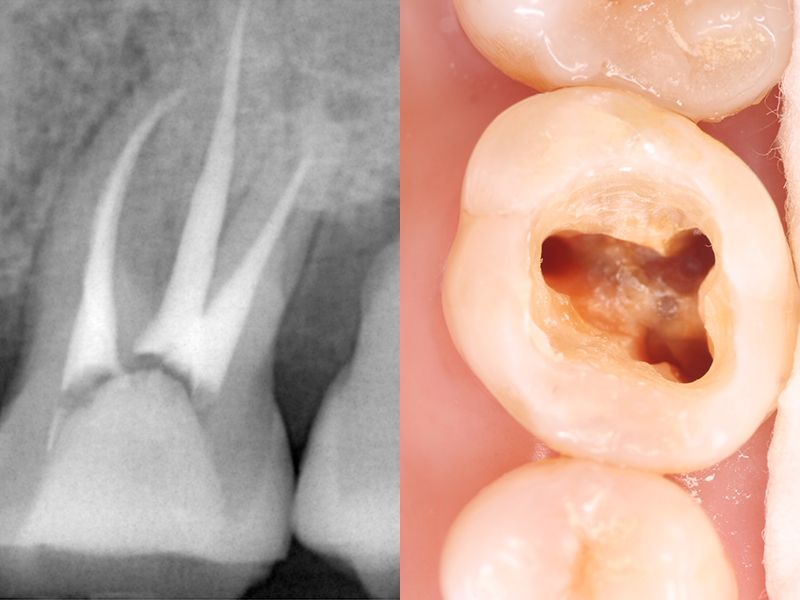

歯の内部には「歯髄(しずい)」と呼ばれる神経や血管を含む組織があります。むし歯の進行や外傷によって、歯髄が細菌に感染したり、壊死したりした場合には、歯髄を除去するための「根管治療」が必要です。

感染した歯髄や血管をそのまま放置してしまうと、炎症が広がり、抜歯のリスクが高まります。根管治療では感染した部分を丁寧に取り除き、消毒を行うことで、歯を抜かずに残せる可能性が高まります。

根管治療とは、細菌によって汚染された歯の根の内部を細い器具(ファイル)で丁寧に除去し、洗浄・消毒を行うことで、根管内の痛みや炎症を抑える治療です。治療後は、根管内に薬剤を充填し、かぶせ物やつめ物を装着することで、歯の機能を再び取り戻します。